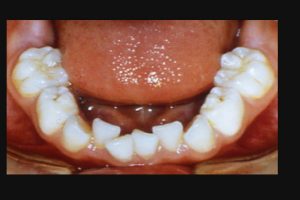

また乳歯の下顎前歯に叢生が認められる小児も、過蓋咬合が多い。(図2)

図2

図2:乳歯なのに叢生の場合、過蓋咬合であることが多い。